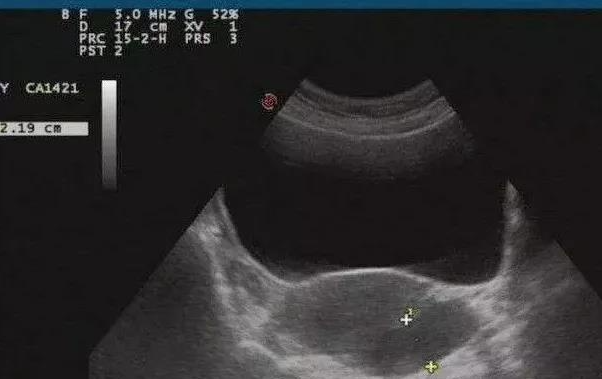

盆腔积液是一种症状,不是一种疾病。严不严重、是否治疗,要看具体情形。

盆腔积液的成分可能是炎性渗出物、卵泡液、囊肿破裂囊内液、血液等;按照病理因素,可分为生理性盆腔积液和病理性盆腔积液两种。

生理性盆腔积液一般不用治疗:如排卵后、月经刚结束时出现少量盆腔积液,没有任何不适症状,可能是卵泡破裂后的卵泡液或是少量月经血倒流至盆腔。这些都是正常现象。